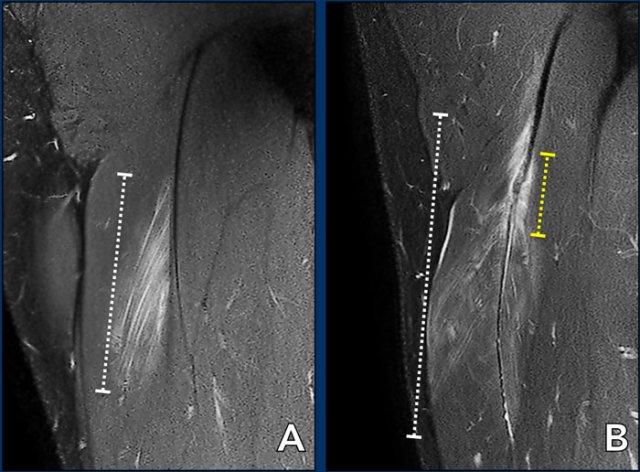

Tổng chiều dài vùng phù nề được ghi nhận (đường chấm trắng). Hãy quan sát kỹ hơn phần gân (đường chấm vàng) và tiếp tục đọc.

Chiều dài đoạn gân biến dạng

Khi gân có hình thái bình thường, khả năng căng giãn ở mức độ thấp.

Gân dày lên, gân có dạng gợn sóng, tăng tín hiệu trong gân đều có thể là dấu hiệu của căng giãn mức độ cao hơn.

Trường hợp 1: gân bình thường.

Trường hợp 2: gân hơi dày và có dạng gợn sóng nhẹ trên một đoạn ngắn.

Trường hợp 3: gân dày rõ rệt và có dạng gợn sóng rõ.

Tất cả các dấu hiệu này cần được mô tả trong báo cáo.

Tổng chiều dài đoạn gân biến dạng được ghi nhận.

Cả chiều dài vùng phù nề và chiều dài đoạn gân biến dạng đều được đo và ghi nhận trong báo cáo.

Trong trường hợp này, tổn thương gân cơ nhị đầu đùi được phân loại là tổn thương bán phần độ 3, do chiều dài vùng phù nề > 15cm (đường chấm trắng) và chiều dài đoạn gân biến dạng > 5cm (đường chấm vàng).

A Phù nề cơ 5-10cm (đường chấm trắng) tại vùng MTJ không kèm biến dạng cấu trúc gân, được phân loại là BAMIC 2b.

B Phù nề cơ >15cm (đường chấm trắng), tại vùng MTJ / gân trong cơ, biến dạng gân > 5cm (đường chấm vàng). Gân có hình ảnh gián đoạn với mất tín hiệu thấp trong lòng gân kèm theo dạng gợn sóng, cho thấy mất sức căng khu trú. BAMIC 3b/c.